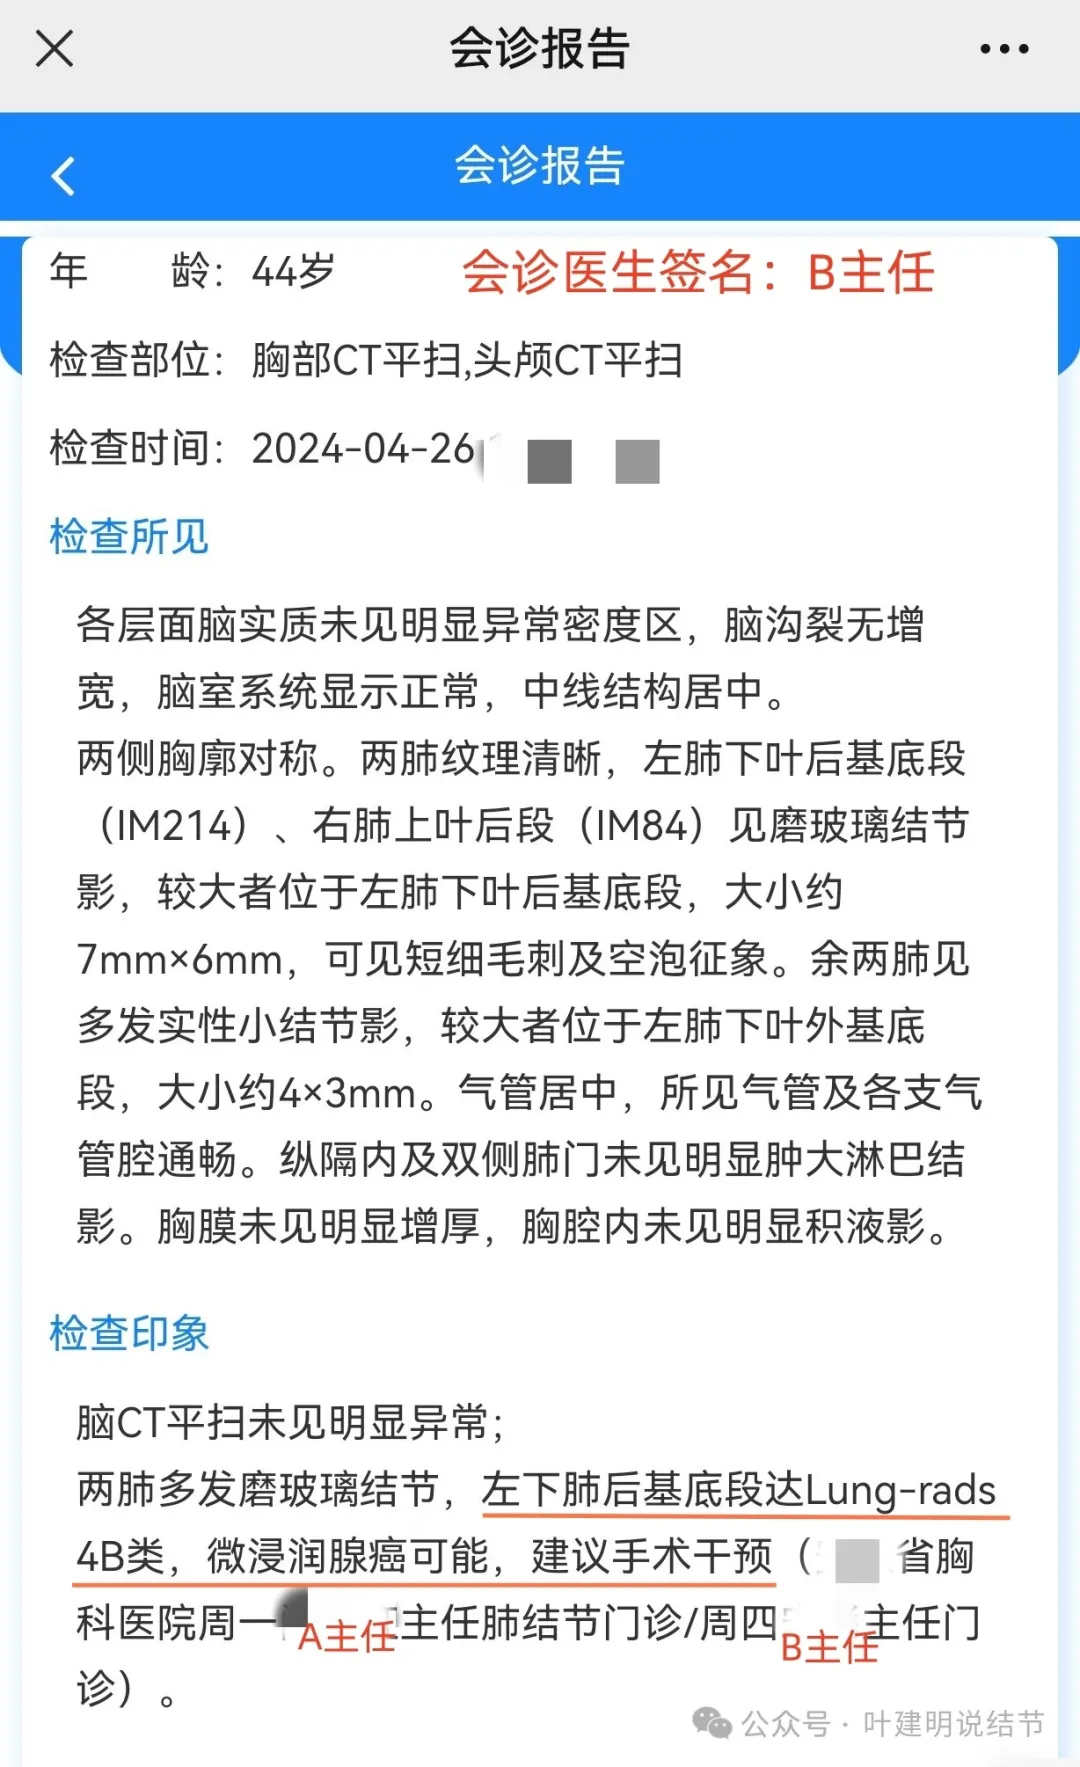

上图是当地的影像报告,印象是两肺多发小结节,随诊。这很非常正常,也是合理的。结果骚操作来了!请该省级胸科医院教授会诊!下面是会诊时的意见:

某省胸科医院医生会诊后给出的意见是:左下肺后基底段(结节)达Lung-rads4B类,微浸润性腺癌可能,建议手术干预。签名的是B医生,后面给出了周一A主任肺结节门诊,周四B主任门诊。大概是团队成员,A医生是著名大咖,B医生是团队骨干成员!